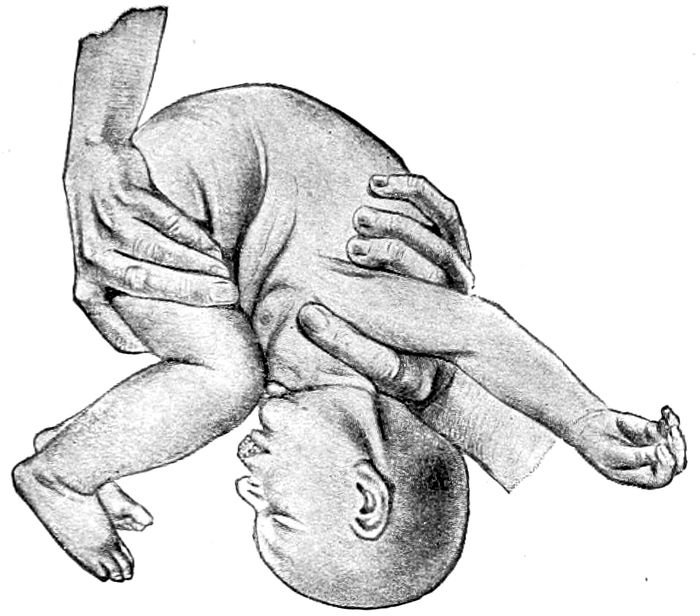

| 118. |

Byrd’s method of artificial respiration. Extension and inspiration |

280 |

| |

| 119. |

Byrd’s method of artificial respiration. Beginning flexion and expiration |

280 |

| |

| 120. |

Byrd’s method of artificial respiration. Flexion and compression |

281 |